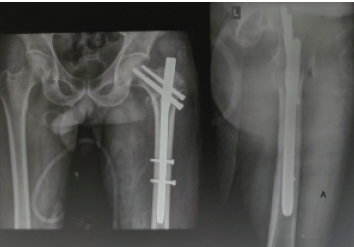

Comparative Study between Proximal Femoral Nail Anti Rotation and Proximal Femoral Nail Anti Rotation Asian to Assessing Functional Outcome